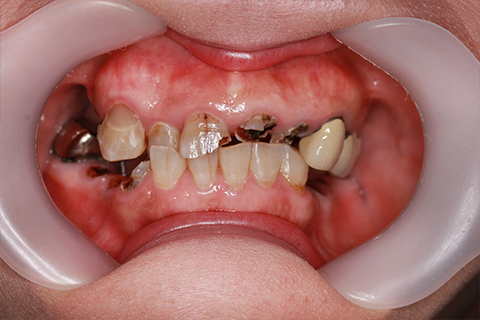

症例4

- 年齢・性別

- 60歳

- 治療期間

- 6ヶ月

- 抜歯

- 残根抜歯のみ

- 治療費

- 198万円

- 備考

- 右上5.6 右下5 左下4.5.6欠損

- 治療内容

- 6本のインプラントを右左側に2回に分けて埋入

- 施術の副作用(リスク)

- オペによる知覚障害。インプラントによる歯肉炎。インプラント脱落。